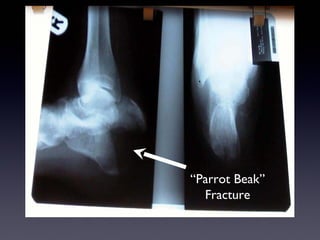

“Parrot Beak”

Fracture

38 year old Female Diabetic Neuropathy